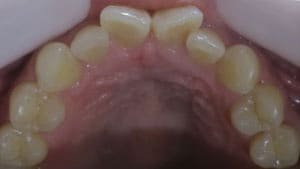

藤沢デンタルオフィスのホワイトニング術前 藤沢デンタルオフィスのホワイトニング術後

術前

術後